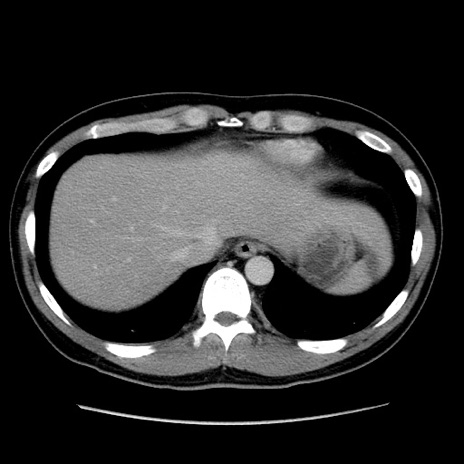

症例4(横断像)

【症例】30歳代男性

【主訴】腹痛、嘔吐

【現病歴】昨晩から突然の腹痛あり、その後嘔吐、軟便も出現。腹痛が改善しないため救急搬送となる。2日前にしめ鯖の食事歴あり。

【身体所見】意識清明、苦悶様、BP 135/90mmHg、BT 35.7℃、腹部:平坦、やや硬、心窩部〜臍部に自発痛、圧痛あり、筋性防御+、反跳痛-

【データ】WBC 8100、CRP 0.57